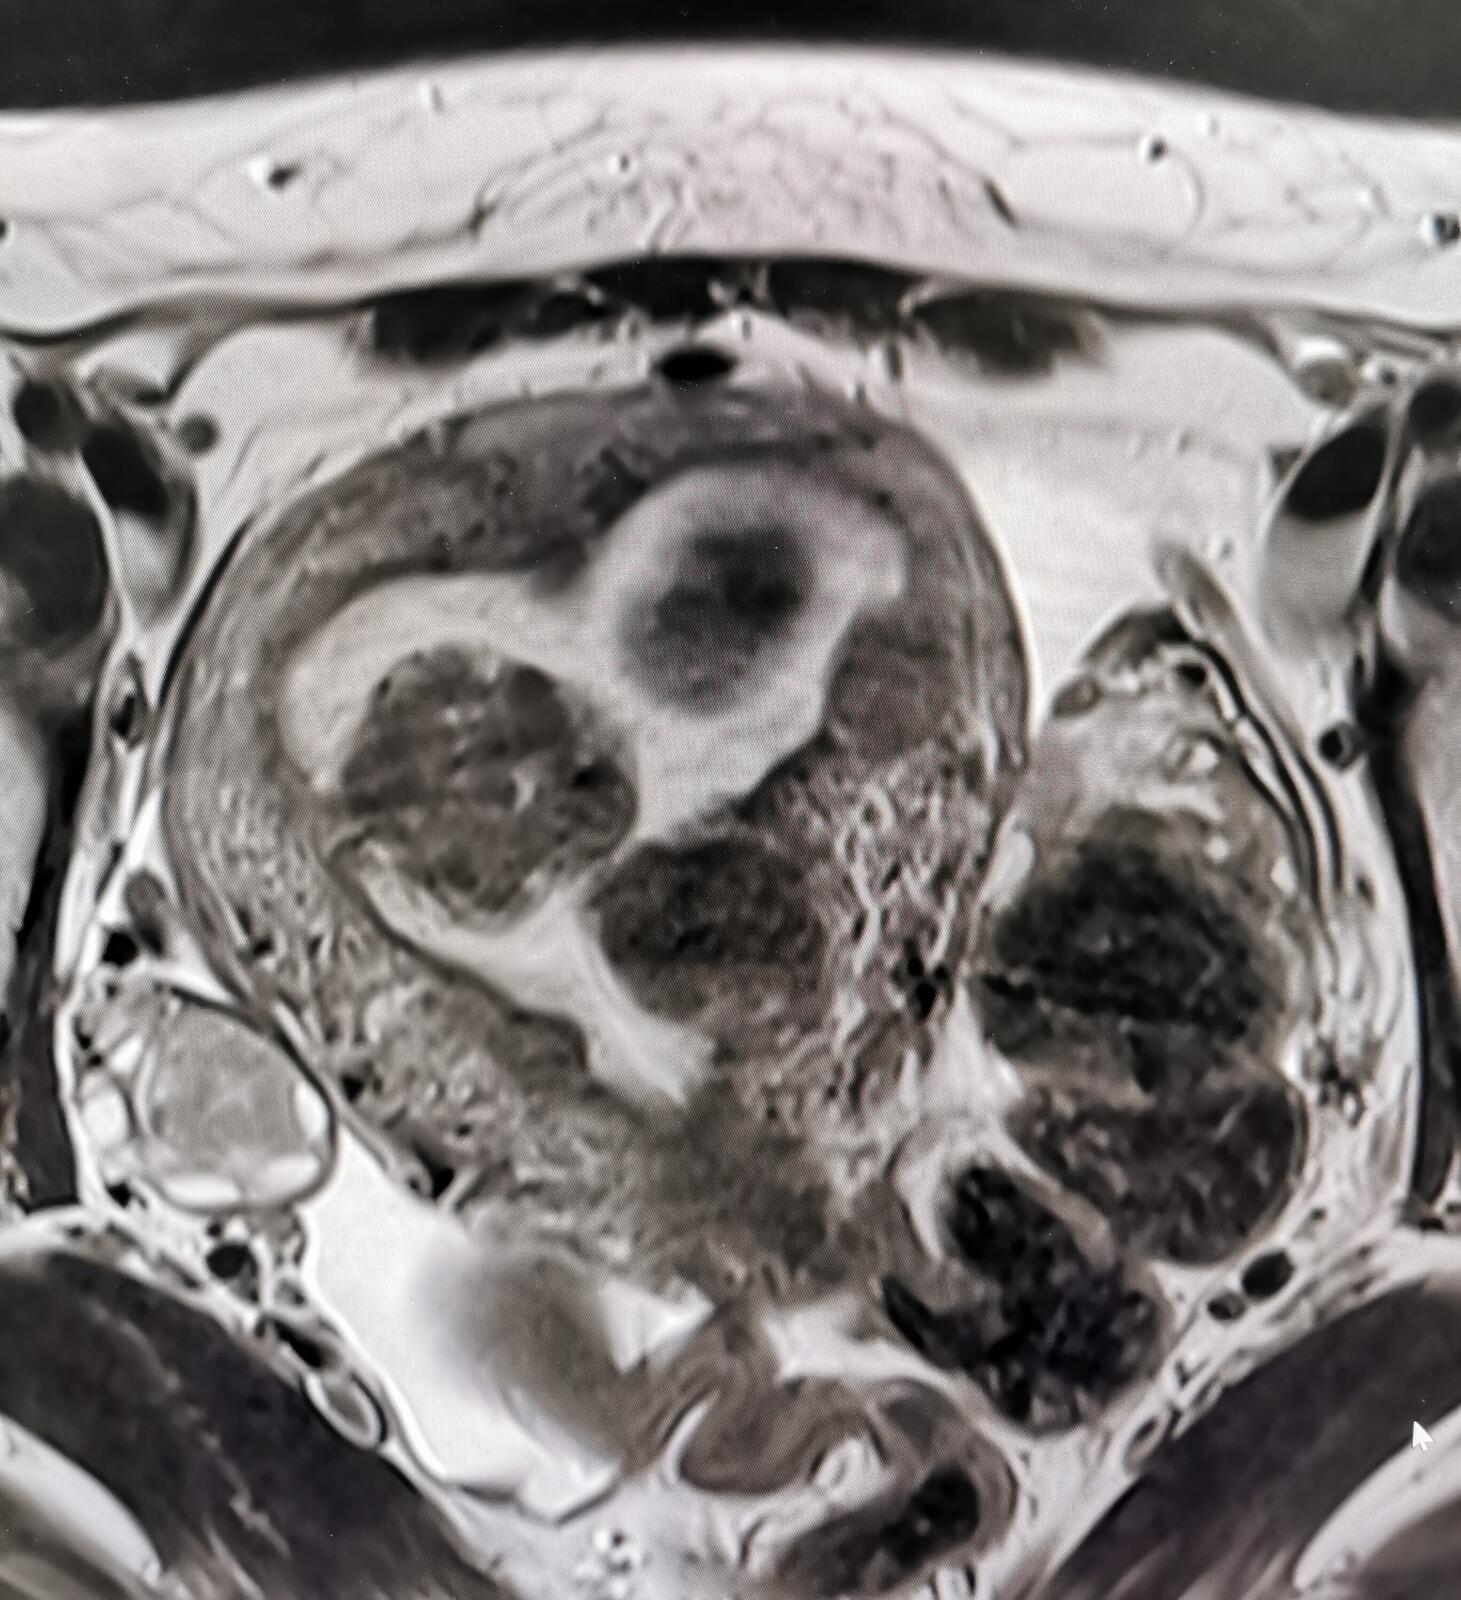

其次综合评估子宫肌瘤大小、位置、数量、位置、磁共振信号和强化特征,这些是确定下一步制定治疗策略的依据

26岁女性,子宫肌瘤治疗前进行磁共振评估,发现有十几个大小不一的子宫肌瘤,很多位于粘膜下,比较大的有蒂,那么宫腔镜一次很难做完,引起宫腔粘连的可能会大一些